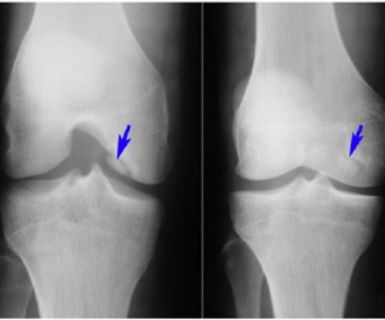

Desde pequeña sufría de una curvatura en las piernas y mis rodillas siempre estaban torcidas. Cada paso era incómodo, y me daba vergüenza usar ropa que dejara ver mis piernas. Los médicos decían que solo con cirugía podría corregirlo, pero me aterraba la idea. Encontré este método y decidí intentarlo. ¡Fue lo mejor que pude hacer! Con dedicación y paciencia, mis piernas se alinearon, y el cambio es evidente. Incluso adjunto mis fotos del antes y después porque yo misma aún me sorprendo Don ver el resultado. ¡Es increíble cómo ha cambiado mi vida!